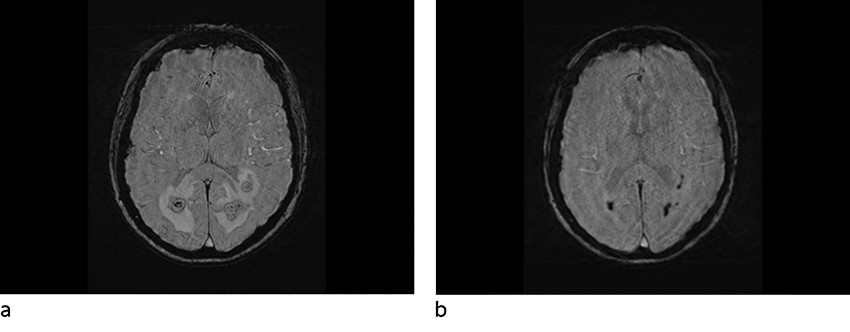

MR caput ble utført om kvelden innleggelsesdagen, ca. ti timer etter at pasienten kom på gastroenterologisk laboratorium. Denne viste multiple runde foci subkortikalt parietooksipitalt bilateralt, med moderat omkringliggende ødem (figur 1, figur 2, figur 3). Lesjonene hadde lavt T2-signal både sentralt og perifert. Det var høy diffusjon sentralt, men en tykk perifer kapsel med betydelig nedsatt diffusjon. Susceptibilitetsvektede sekvenser (SWI) viste signalbortfall både perifert og i punktformede områder sentralt, noe som kunne være blodnedbrytningsprodukter eller paramagnetiske elementer (jern, magnesium, sink, nikkel). Det var lett forhøyet T1-signal i enkelte lesjoner, hvilket også kunne tyde på innhold av blodnedbrytningsprodukter. I tillegg var det en tynn, lobulert kontrastoppladning i periferien av lesjonene, stedvis med uskarpe grenser mot omkringliggende parenkym.

Disse karakteristikaene ved lesjonene hos en immunsupprimert pasient med tegn til infeksjon gav mistanke om soppabscesser, mest sannsynlig forårsaket av Aspergillus sp.

Hjerneabscesser kan ha variable bildediagnostiske utrykk avhengig av agens og utviklingsstadier (4). Man kan ikke bestemme agens ut fra MR-undersøkelse, men karakteristika på standardsekvenser, diffusjonsvektede sekvenser (DWI) og susceptibilitetsvektede sekvenser kan brukes for å skille pyogene abscesser fra soppabscesser (4–6). Av sekvensene synes de diffusjonsvektede å være de mest sensitive for tidlig identifikasjon av cerebral aspergillose (5). Disse er også nyttige i differensieringen mellom soppabscesser og pyogene abscesser (tabell 1) (5). Begge kan vise diffusjonsrestriksjon i hulrom, men bakterielle abscesser har ofte homogen diffusjonsrestriksjon sentralt, i motsetning til soppabscesser, der signalet er inhomogent. Soppabscesser viser også typisk diffusjonsrestriksjon i veggene, noe som er uvanlig ved pyogene abscesser (5). Aspergillusabscesser er ofte multiple, med lobulerte konturer, ujevne indre grenser og variabel kontrastoppladning i periferien (4, 5). På T2-sekvenser og susceptibilitetsvektede sekvenser fremstilles lav intensitet sentralt, grunnet høy forekomst av paramagnetiske elementer (jern, magnesium, sink, nikkel), som er viktig for soppens vekst. Dette er uvanlig ved pyogene abscesser. Ved aspergillusabscesser kan man se hemoragisk nekrose (4, 5).